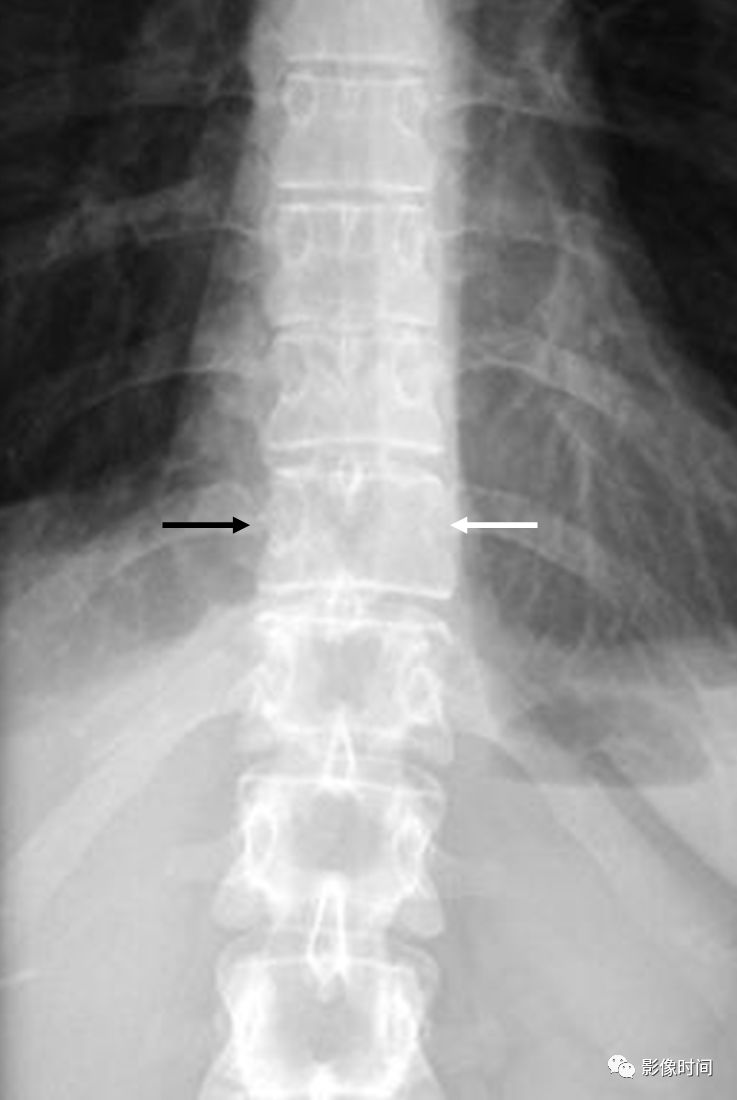

椎弓根征,又称眨眼猫头鹰征(Winking owl sign)

本征指的是在脊柱正位 X 线片上,一侧椎弓根投影消失,为「闭一只眼」(箭示),另一侧椎弓根投影存在,为「睁一只眼」(圈),相应棘突类似喙,总体形似一只眨眼的猫头鹰。

病例 1. 女,37 岁,腰痛 4 月余,肺癌转移。腰椎正位片,示第 3 腰椎右侧椎弓环影破坏消失。

病例 2. 胸椎转移瘤。正位 X 线片示胸 11 左侧椎弓根投影消失(白箭),右侧椎弓根影存在(黑箭),形似眨眼的猫头鹰。